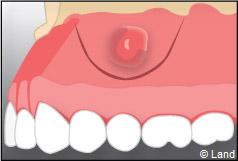

La perte du caillot risque d’entrainer une infection osseuse douloureuse appelée alvéolite.

Une fois la dent enlevée, la cavité est nettoyée. En cas d’une dent souffrant d’inflammation, le tissu infecté sera également enlevé.